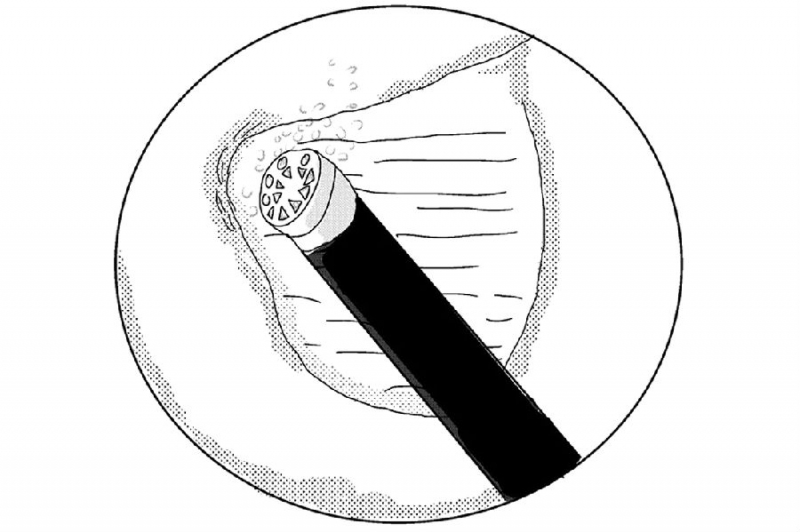

3. 使用4mm金刚砂磨钻将椎板下缘及下关节突内缘磨薄;